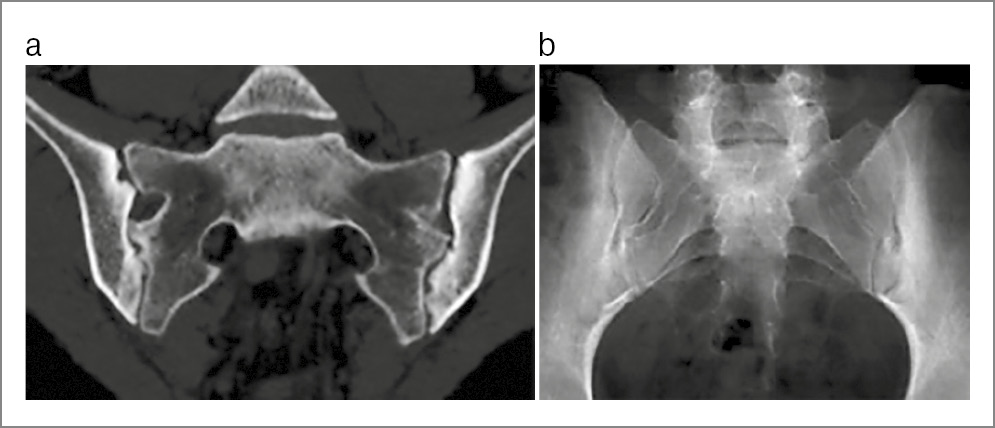

Рис. 4. Пациентка П., диагноз АС, длительность болезни 12 мес: a – КТ крестцово-подвздошных сочленений (коронарная проекция) показала широкий субхондральный склероз подвздошных костей, краевые эрозии подвздошных костей и крестца, расширение суставной щели с обеих сторон (двусторонний определенный сакроилиит); b – на рентгенограмме крестцово-подвздошных сочленений этой же пациентки (сделана незадолго до КТ) изменения (субхондральный склероз, подозрение на расширение щели в средней части левого сустава) видны далеко не так отчетливо, как на КТ.